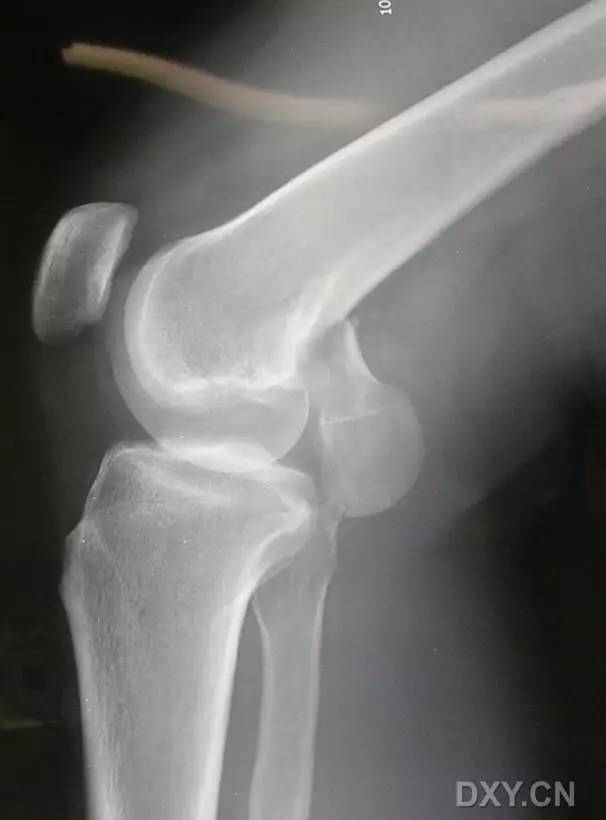

5. Hoffa 骨折

指股骨远端冠状面的骨折。

病例 1:一般股骨髁间、髁上粉碎骨折中含 Hoffa 骨折的不少见,但单纯后髁骨折则很少见。

正位片

侧位片

水平位 CT

第 2 例

第 3 例